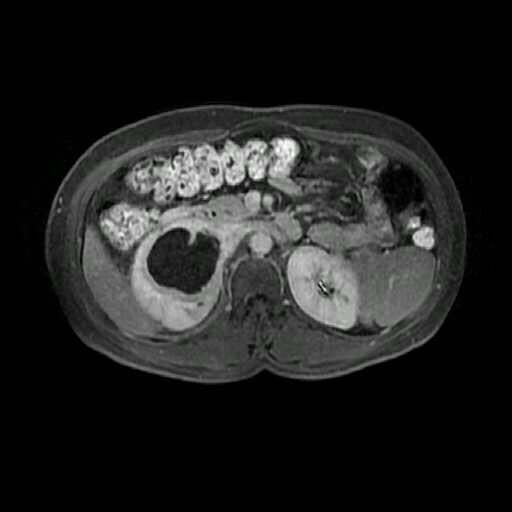

肾癌 ( renal carcinoma )